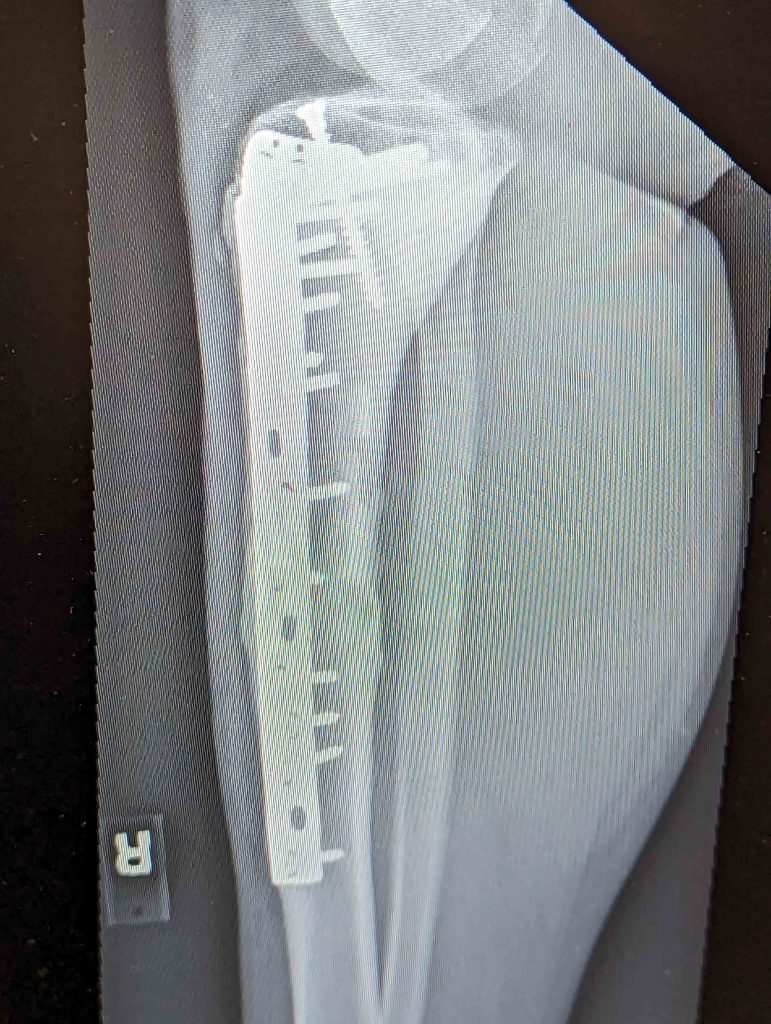

I had surgery on my leg on June of summer 2010.

They performed a limb salvaging, replacing my tibia with a cadaver bone, anchored with titanium rod and screws. The hope was my bone would fuse to the cadaver bone over time.

Fortunately, they found a match, and my surgery was successful.

As far as my leg, after surgery I regained most of the normal function. I used to run and play basketball, but after a few years it became too much, and I had to stop. Still, I’m grateful to have a functioning leg. Medicine has come a long way; if it had been 10 years earlier at the time of my surgery, they may have just amputated it.